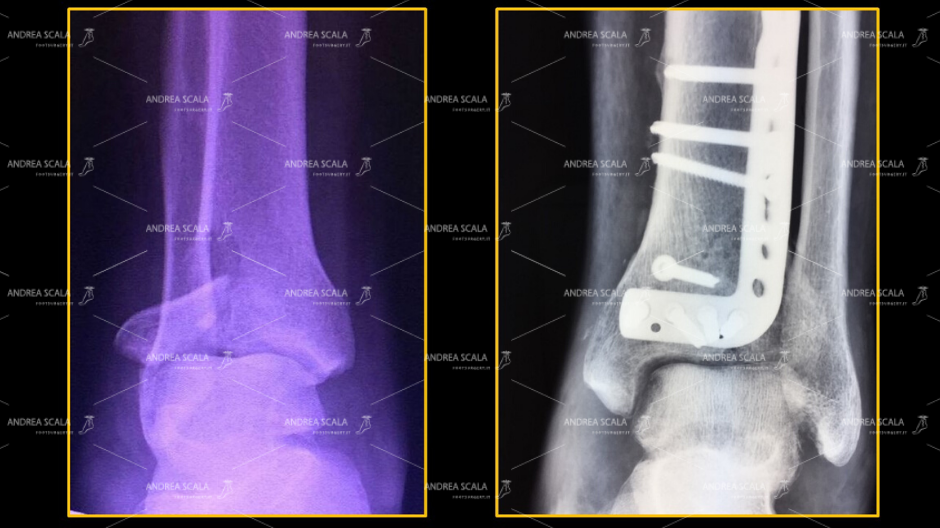

La FRATTURA DEL PILONE TIBIALE. Con frattura del pilone tibiale si intende una lesione scheletrica a carico della regione meta–epifisaria distale della tibia, che comprometta la quasi totalità della superficie articolare tibiale sottoposta al carico, e che è associata frequentemente ad una frattura del perone.

2) FRATTURA DELLA TIBIA E DEL PERONE La grande varietà delle fratture scheletriche vengono comprese in diversi sistemi di classificazione che tengono conto della localizzazione anatomica delle fratture, del coinvolgimento della superficie articolare della tibia ( “PLAFOND TIBIALE” ), energia del trauma , coinvolgimento dei tessuti molli, esposizione della frattura.

La principale regola chirurgica è quella di cercare quanto più possibile la riduzione anatomica dei frammenti della frattura. Questa regola diventa un obbligo nei casi di frattura delle articolazioni, come avviene per tutte le fratture che coinvolgono le articolazione dello scheletro.

I risultati clinici a distanza non sono omogenei e risultano molto variabili anche in centri traumatologici di grande esperienza. Molto spesso si osservano interventi molto ben eseguiti in cui la frattura risulta ricomposta molto bene con placche e viti disposte in modo adeguato, in cui la mobilità articolare il risultato funzionale risultano molto deludenti sia per il paziente che per il chirurgo.

La frattura risulta ricomposta molto bene con placche e viti disposte in modo adeguato, in cui la mobilità articolare il risultato funzionale risultano molto deludenti sia per il paziente che per il chirurgo.